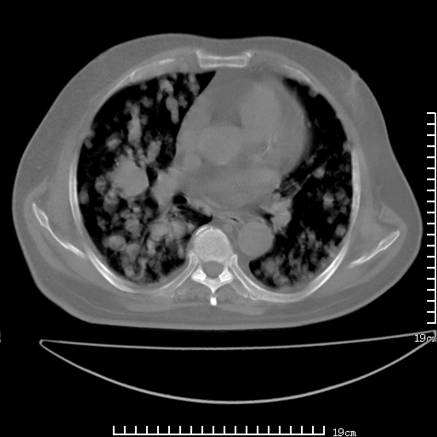

张男,75岁,干咳半年余,小便不利二年,b超检查前列腺增大,未见明显肿块;前列腺癌血生化检查多项指标明显增高。

双肺内多发转移瘤,纵膈淋巴结转移。来源前列腺?建议盆腔mri进一步检查。

双肺转移满了。

两肺广泛转移瘤。